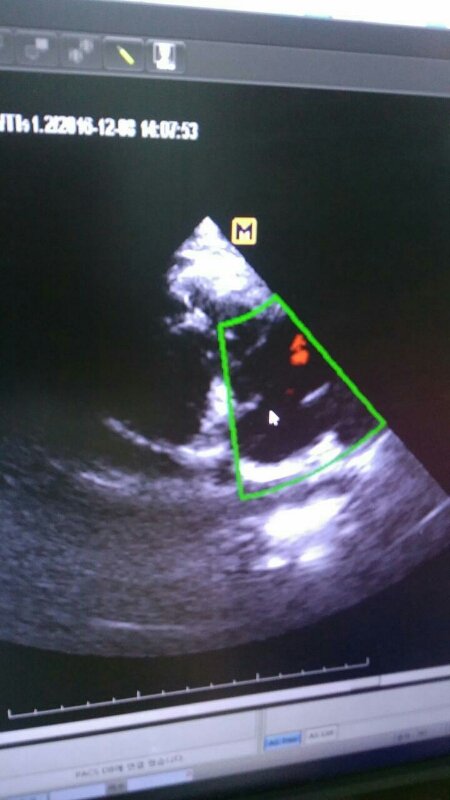

심장에 작은 구멍이 있지만 살아가는대 큰 지장은 없을듯 하다고 하십니다.